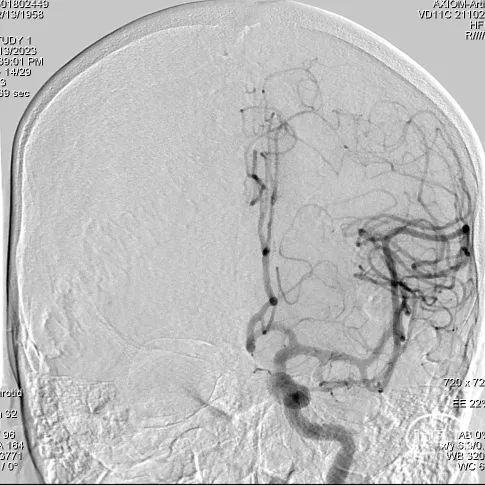

右侧颈内动脉造影

右侧椎动脉造影

① 右侧椎动脉V4段夹层动脉瘤伴血栓形成;

长鞘到位后工作角度造影;尽量暴露双椎汇合部,方便术中判断支架头端锚定位置。

造影提示YonFlow®血流导向密网支架头端和后半段打开良好。

术后造影。

蒙片提示支架展开良好。

术后半年复查造影:YonFlow®血流导向密网支架贴壁良好,载流动脉前向血流良好。